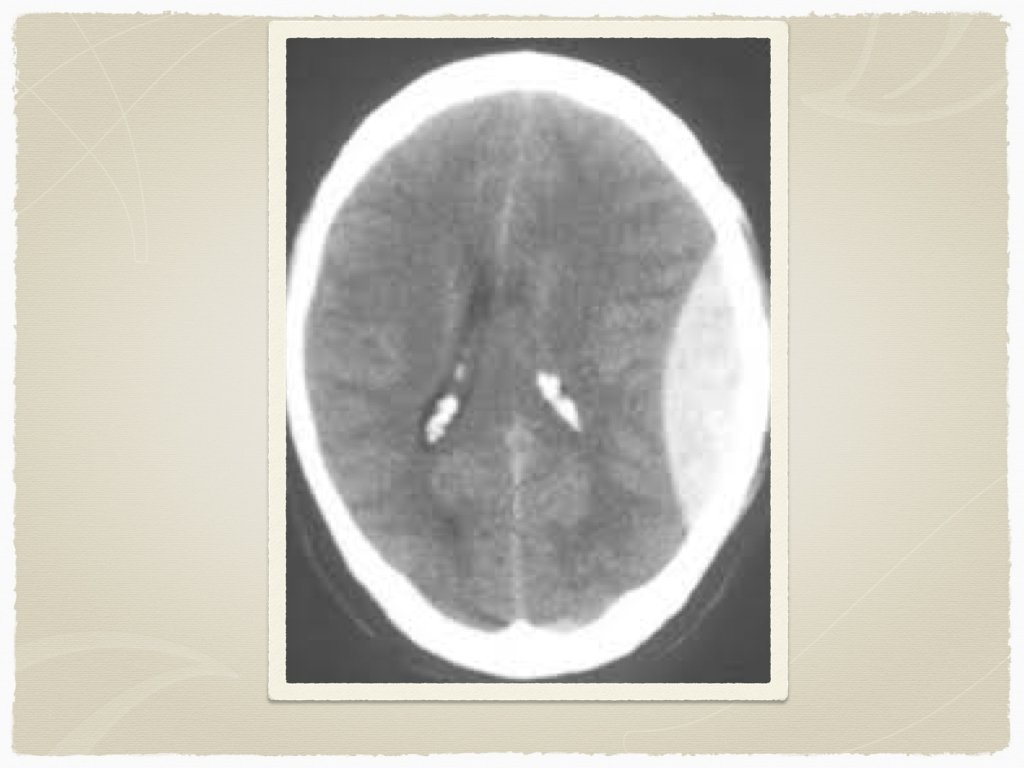

Outside of the window for TPA - Diagnosis CT head: findings? early vs late findings?

Diagnostics CT is the initial test of choice In sentinel bleed for aneurysmal SAH, can be negative LP to follow if suspicion Lab work: INR Troponin ECG